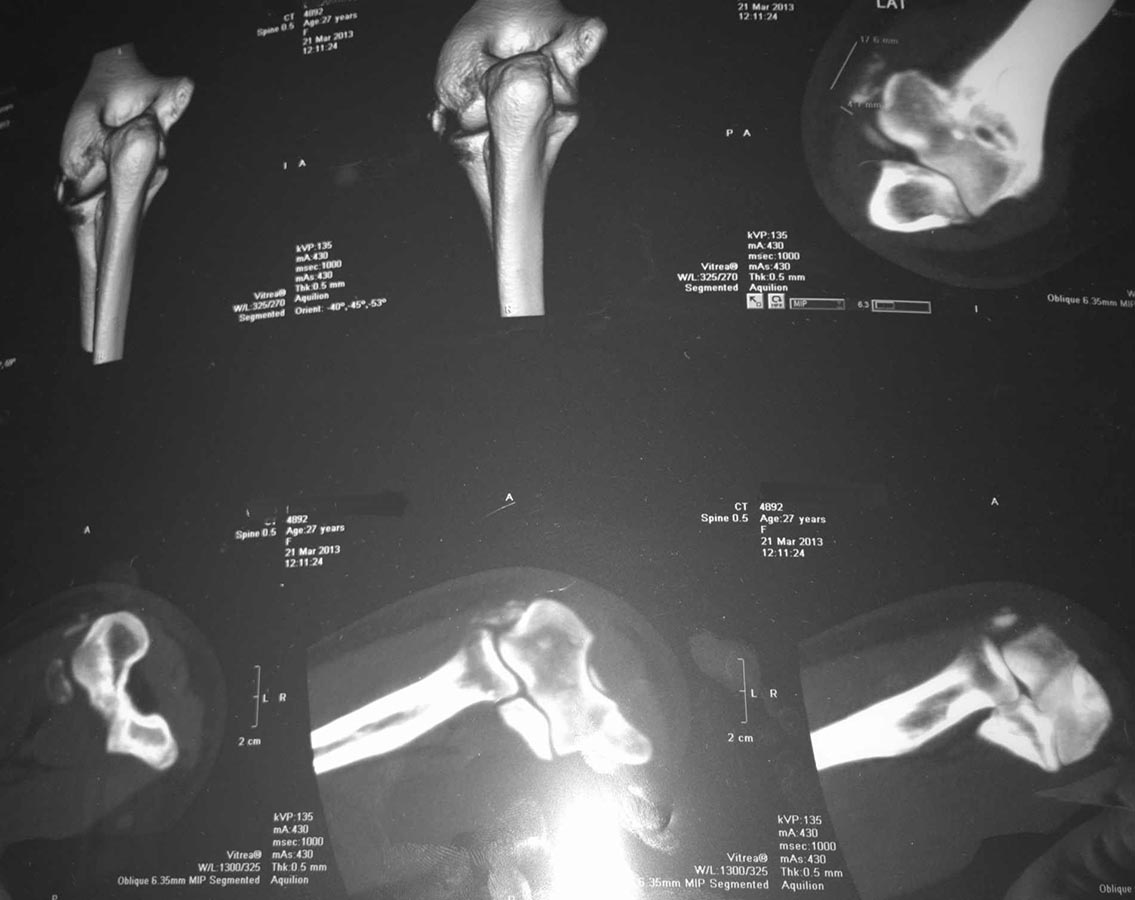

"Мне 27 лет. 15 марта заболела рука (левая; и я НЕ левша) в области локтевого сустава; не падала, тяжести не таскала, может недели за две до этого немного стукнулась локтем, но я полагаю, что если бы это было причиной, то боль появилась бы сразу, а не через 2 недели. Для общей картины еще-в 1995 году был перелом локтевой кости(трещина) и лучевой (закрытый со смещением) в области лучезапястного сустава). Симптомы: боль в локтевом суставе при сгибании\разгибании. Больно,но терпеть можно. 16 марта: рука ограниченно движется-процентов на 40 из всего во возможного, боль усилилась, Сделали рентген( в больнице "X")-поставили диагноз- латеральный эпикондилит.С 17 марта боль стала адской, рука отекла, шевелить невозможно даже пальцами, Все предплечье сковала сильнейшая непроходящая судорога(спазм). Рука онемевает, В пальцах чувствительность снижена. Боль вызывал даже воздух,попадающий на руку. Делала инъекции внутримышечно -мовалис(по 1 ампуле\3 дня), и дексалгин(по 3 ампулы в день\по настоящее время)-получается в день 4 инъекции. Мази прописанные я не использовала, т.к. к руке прикосаться невозможно. Боль остается и по сей момент, хотя уже могу шевелить пальцами, и дексалгин ставлю 2 раза в сутки. К постоянной судороге добавилось еще периодическое подергивание током (не знаю как описать правильно это, но так же, когда локтем стукаешься и током фигачит ). Ах да..сегодня гипс наложили ("на всякий случай"(с) )Температура нормальная (за исключением нескольких дней, когда без обезболивающего еще была-навыла себе температуру до 37.5 ), анализ крови не делали. Ревматолог сказала, что это не по ее профилю. Поэтому бегаю от хирурга к травматологу и обратно."Для какой болячки может быть характерна такая клиника и картинка? Для латерального эпикондилита такая "отшнуровка" нехарактерна. В каком направлении размышлять, какое дообследование назначить?

Фрагмент, который определяется на снимке, на мой взгляд, это оссификация коллатеральной связки. А вот как связать оссификацию с такой неврологической симптоматикой - не представляю.

На снимках похоже на рассекающий остеохондрит медиального надмыщелка плечевой кости

Проблема в том, что проблема латерально, а с этой стороны таких фрагментов не бывает

Нет ли перелома головки ЛУЧЕВОЙ кости с невропатией лучевого нерва?

Может быть отрыв наружного надмыщелка плеча,постепенное (в течение двух недель) стягивание костных фрагментов прикрепляющимися мышцами в дистальном направлении до суставной щели + процесс рубцевания, привели к травматической невропатии глубокой ветви лучевого нерва,усилению болей? Тогда ревизия головчато-лучевого сустава,невролиз глубокой ветви лучевого нерва,подшивание проксимального конца мышцы (с костным фрагментом или без) к наружному надмыщелку.